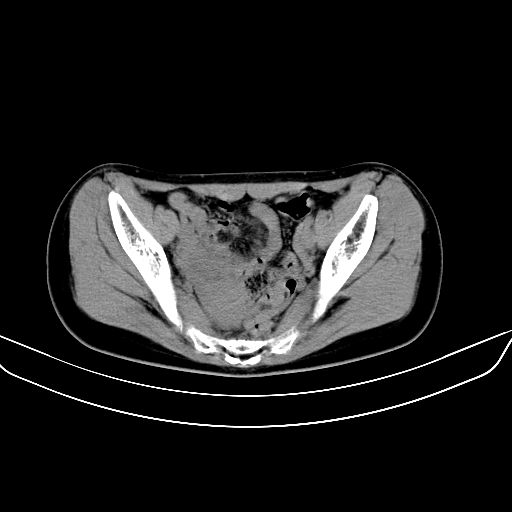

以下是引用zsl6918在2008-7-11 21:40:00的发言:[br]双侧骶髂关节骨质破坏以下三分之一为主,符合强直性脊柱炎表现

以下是引用zhangzhongshou在2008-7-11 21:41:00的发言:[br]患者是女性,hla-b27抗原(—),首先不太考虑强直性脊柱炎,建议查类风湿因子,骶髂关节改变考虑类风湿性关节炎可能性大,建议进一步检查。